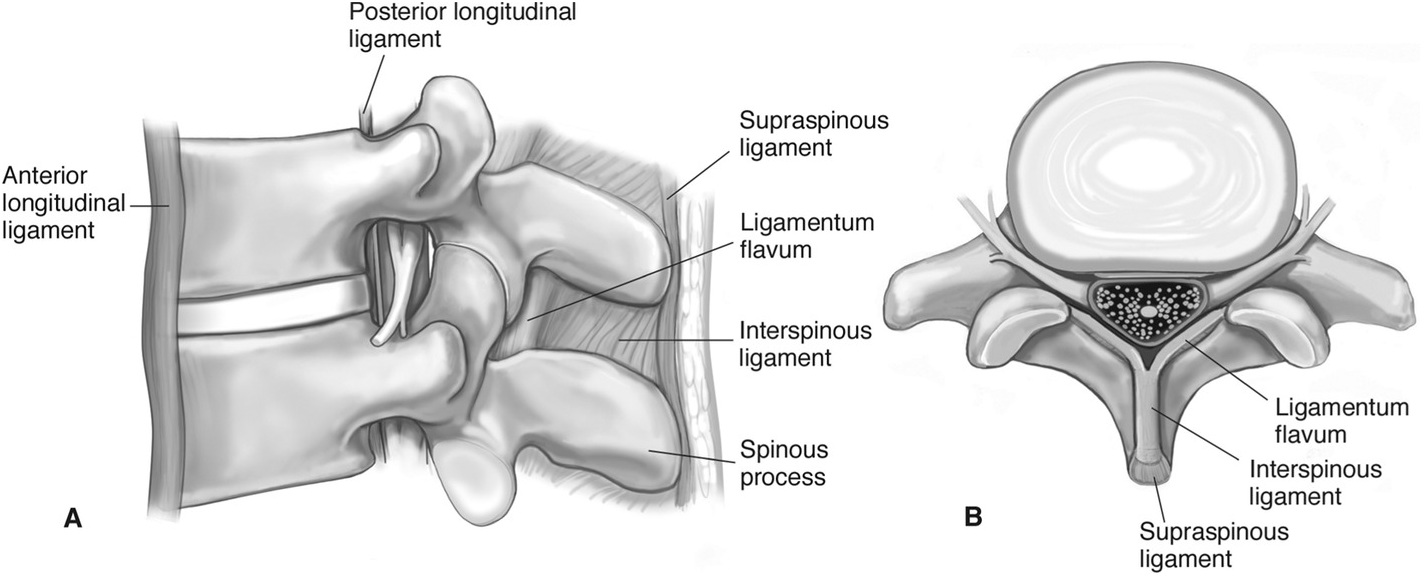

Pure Health - Anatomy 101 - Supraspinous ligament and interspinous ligament 📚 The supraspinous ligament and interspinous ligament work together to limit flexion of the spine by limiting separation of the spinous

DOCS - The interspinous ligament is located between the spinous processes of adjacent vertebrae in the spine. It extends from the base of one spinous process to the apex of the next,